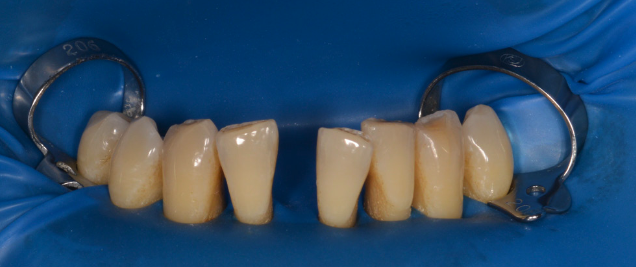

Având în vedere că se folosește un sistem adeziv, dinții se izolează cu diga dentară, care are rolul unei izolări perfecte de restul mediului bucal și reduce contaminarea cu salivă sau sânge. Dinților extrași sau pierduți li se reduce din lungimea rădăcinii, pentru a putea fi repozitionați estetic în poziția corectă. Ei nu mai primesc vascularizație și inervație, doar se sprijină la nivelul gingiei. (Fig. 5.4.3).